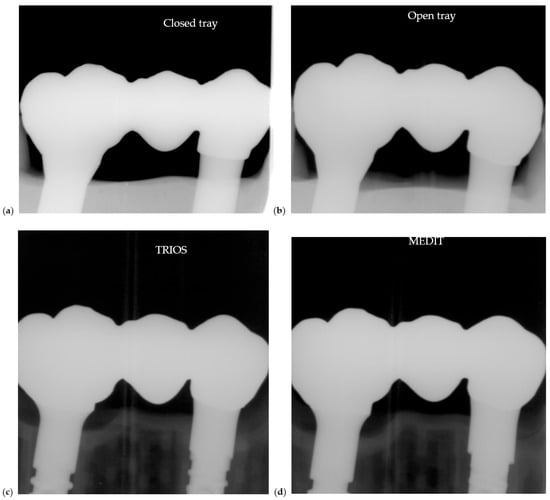

All models were fitted with the same soldered verification bar (Figure 11). These radiographs were used to assess passive fit and impression accuracy under identical test conditions.

Figure 11.

Radiographic comparison of soldered test bars on models fabricated with different impression techniques: (a) closed tray conventional impression, (b) open tray impression, (c) TRIOS scan and (d) MEDIT scan.

Radiographs were taken to assess passive fit, abutment–restoration interface alignment, and potential marginal gaps under clinical torque values (Figure 12).

Figure 12.

Radiographic evaluation of Zirconia restorations seated on models fabricated with different impression techniques: (a) closed tray conventional impression, (b) open tray impression, (c) TRIOS scan and (d) MEDIT scan.